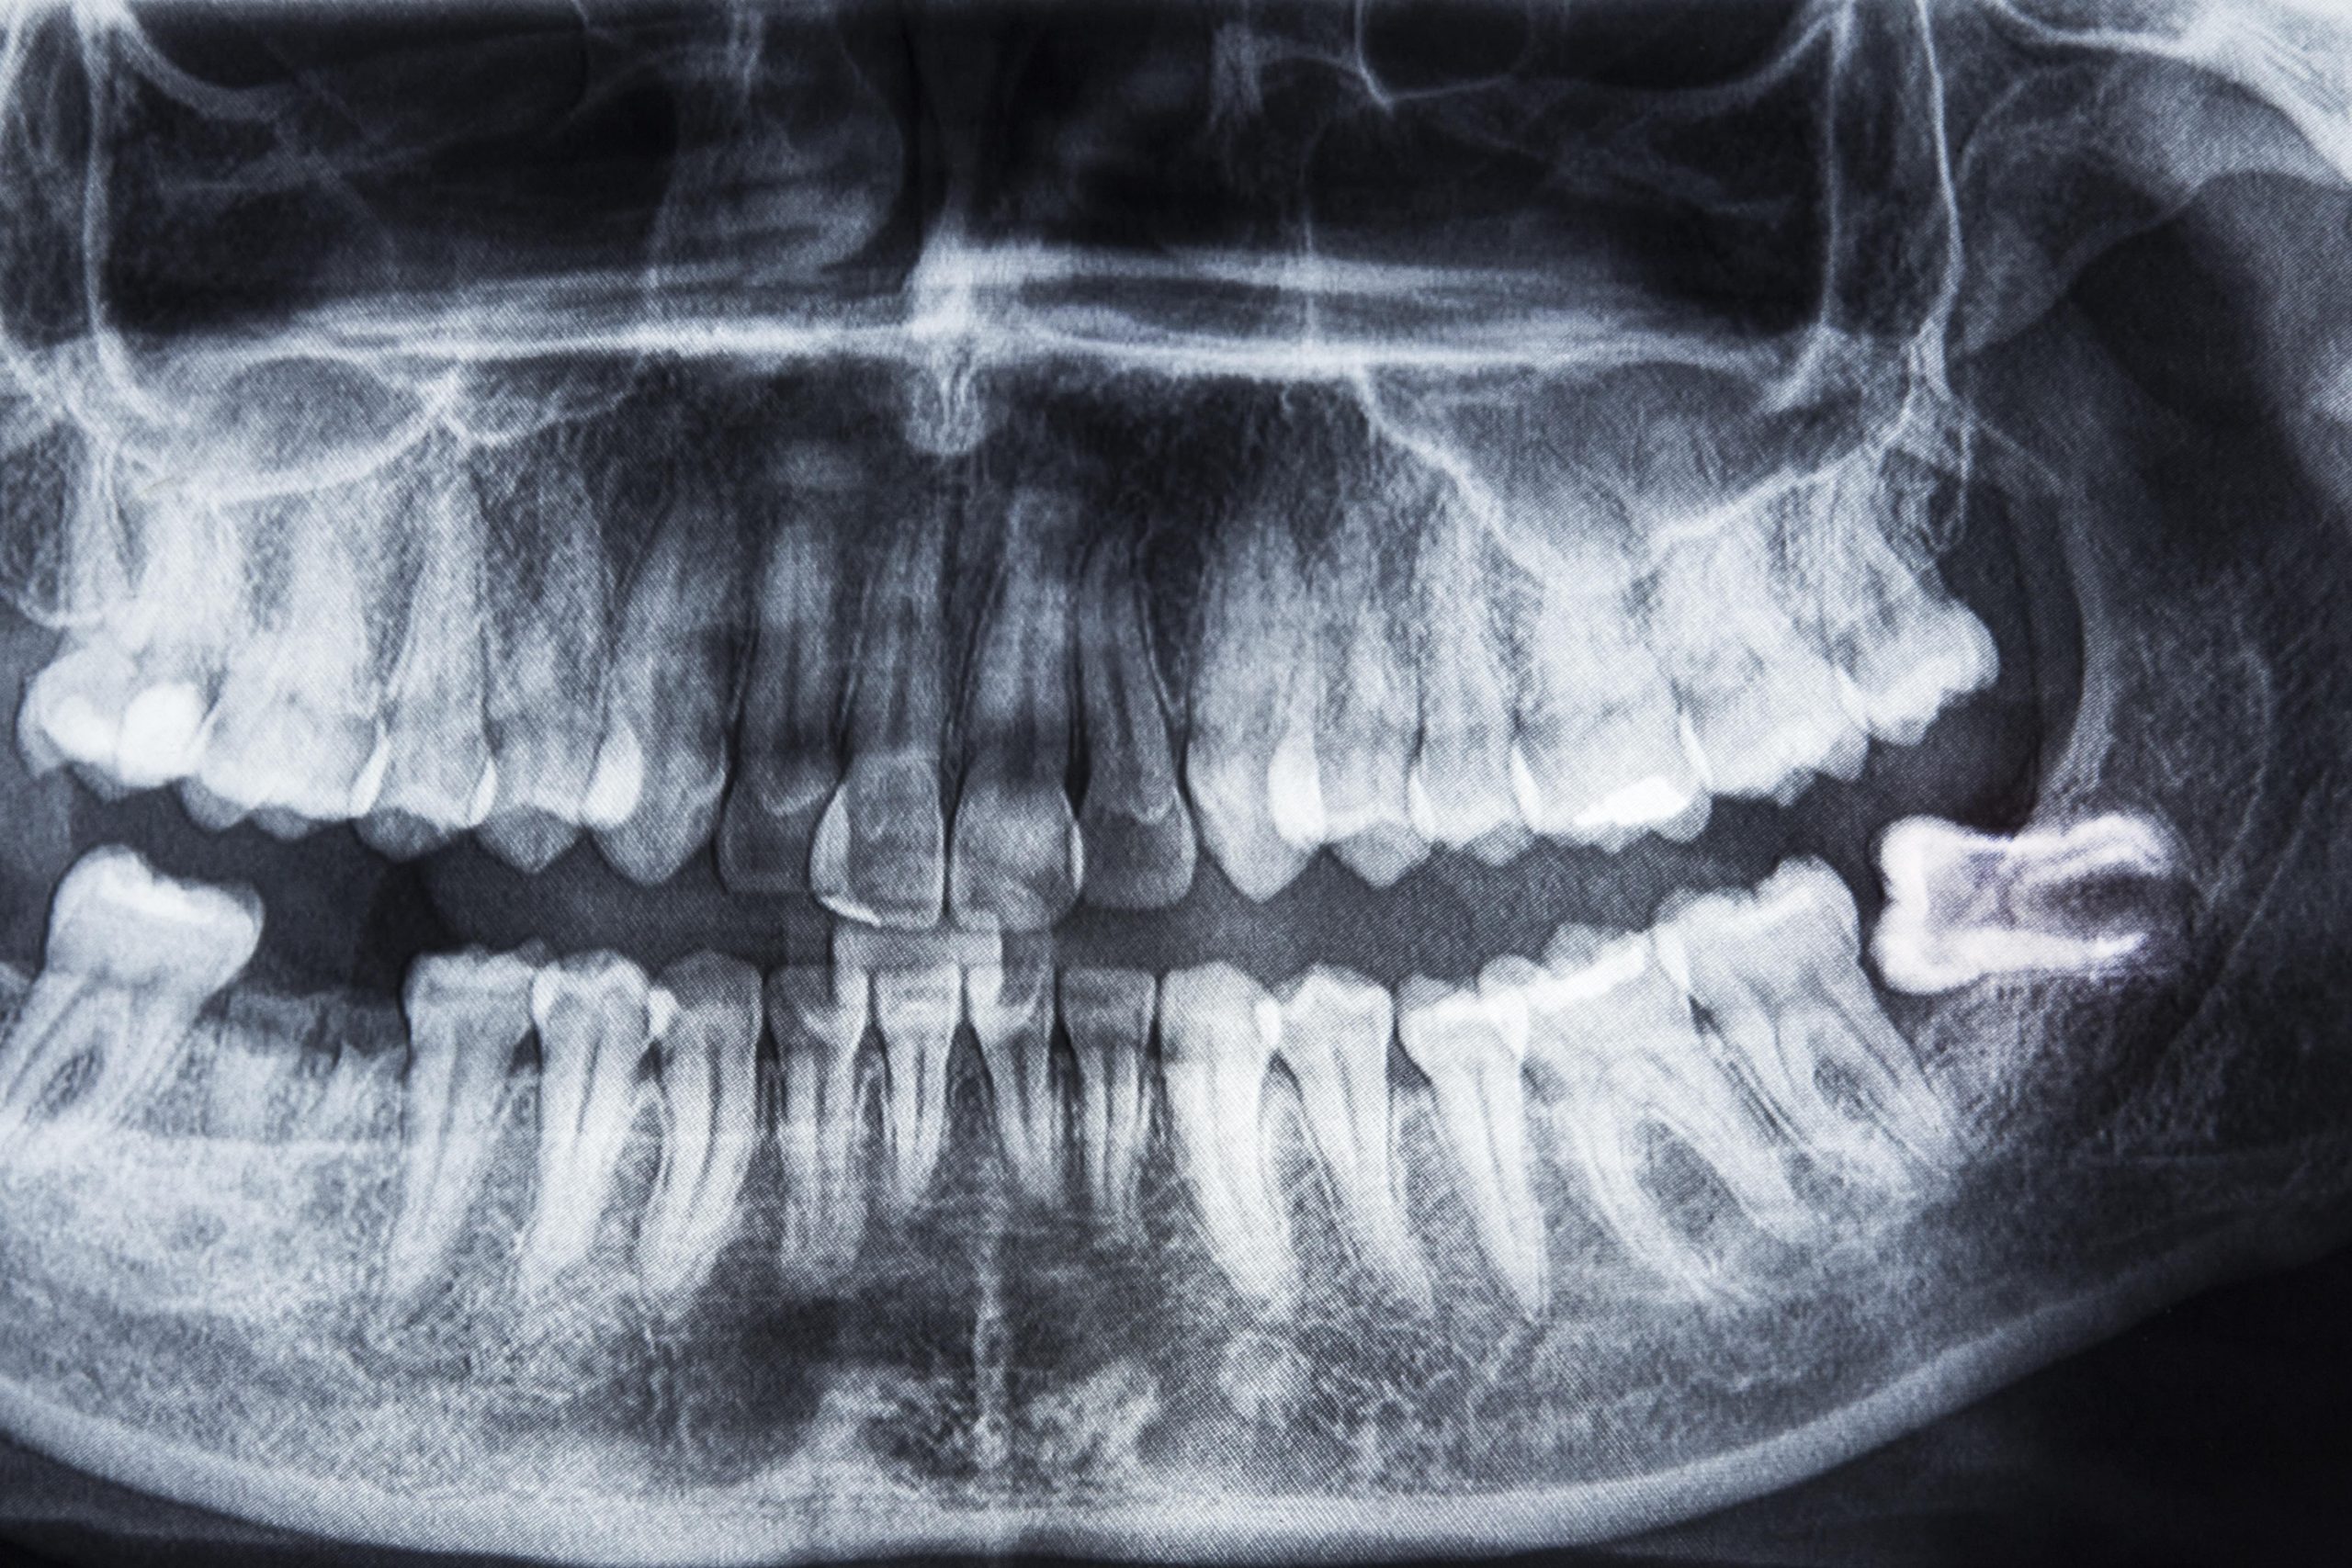

I denti del giudizio, noti anche come terzi molari, sono i denti situati nella parte posteriore della bocca, alla fine della fila di denti. Sono gli ultimi denti permanenti ad erompere e solitamente - negli individui in cui compaiono - spuntano tra i 17 e i 25 anni, da qui il loro nome comune di "denti del giudizio".

A causa della possibile mancanza di spazio nella bocca, questi denti possono causare diversi problemi come infiammazioni, infezioni, dolore e spesso richiedono l’estrazione. Pertanto, è importante consultare un dentista per una valutazione accurata e un eventuale trattamento dei denti del giudizio.

Grazie anche a radiografie panoramiche e/o 3D, lo specialista esamina la situazione, soppesando rischi e benefici a lungo termine di un’estrazione o viceversa di una non-estrazione.